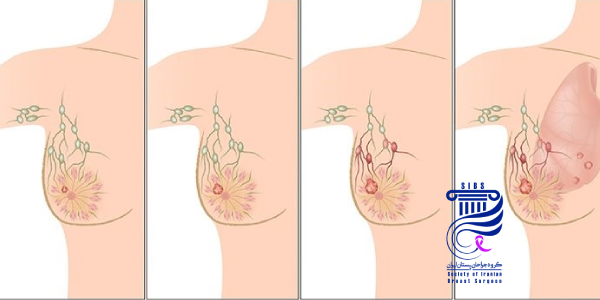

جراحی سرطان سینه، با هدف برداشتن تودههای سرطانی، کاهش گسترش بیماری و افزایش احتمال بهبودی انجام میشود و بسته به نوع و مرحله سرطان، روشهای مختلفی مثل ماستکتومی (برداشتن کامل سینه) یا لامپکتومی (برداشتن توده با حفظ سینه) مورد استفاده قرار میگیرد. تصمیمگیری درباره نوع جراحی با در نظر گرفتن عواملی نظیر اندازه تومور، محل آن، وضعیت غدد لنفاوی و شرایط کلی بیمار انجام میشود.

تعیین نوع جراحی مناسب بستگی به عواملی چون اندازه، محل و مرحله سرطان سینه دارد. دو نوع اصلی جراحی شامل لامپکتومی (برداشتن تنها توده سرطانی) و ماستکتومی (برداشتن کامل سینه) است. در برخی موارد، برای برداشتن غدد لنفاوی زیر بغل نیز نیاز به جراحی است. پزشک با توجه به شرایط بیمار، نوع جراحی مناسب را انتخاب میکند تا بهترین نتیجه درمانی حاصل شود.

بررسی غدد لنفاوی

بررسی بزرگی غدد لنفاوی در سرطان سینه به منظور تشخیص گسترش سرطان به غدد لنفاوی انجام میشود. این غدد در زیر بغل قرار دارند و اگر سرطان به آنها گسترش یابد، نشان دهنده پیشرفت بیماری است. برای بررسی وضعیت غدد لنفاوی، از بیوپسی یا نمونه برداری استفاده میشود تا مشخص شود سرطان به این غدد سرایت کرده است.